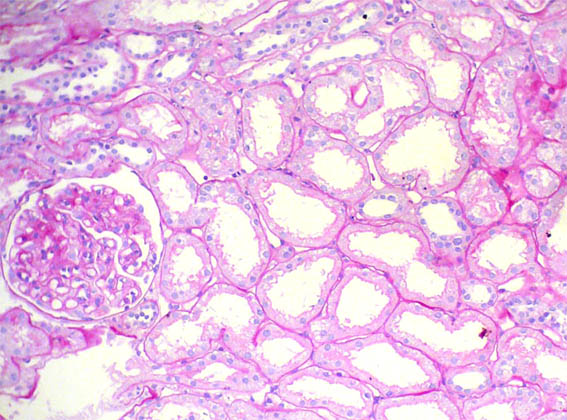

Figure 1. H&E , X200.